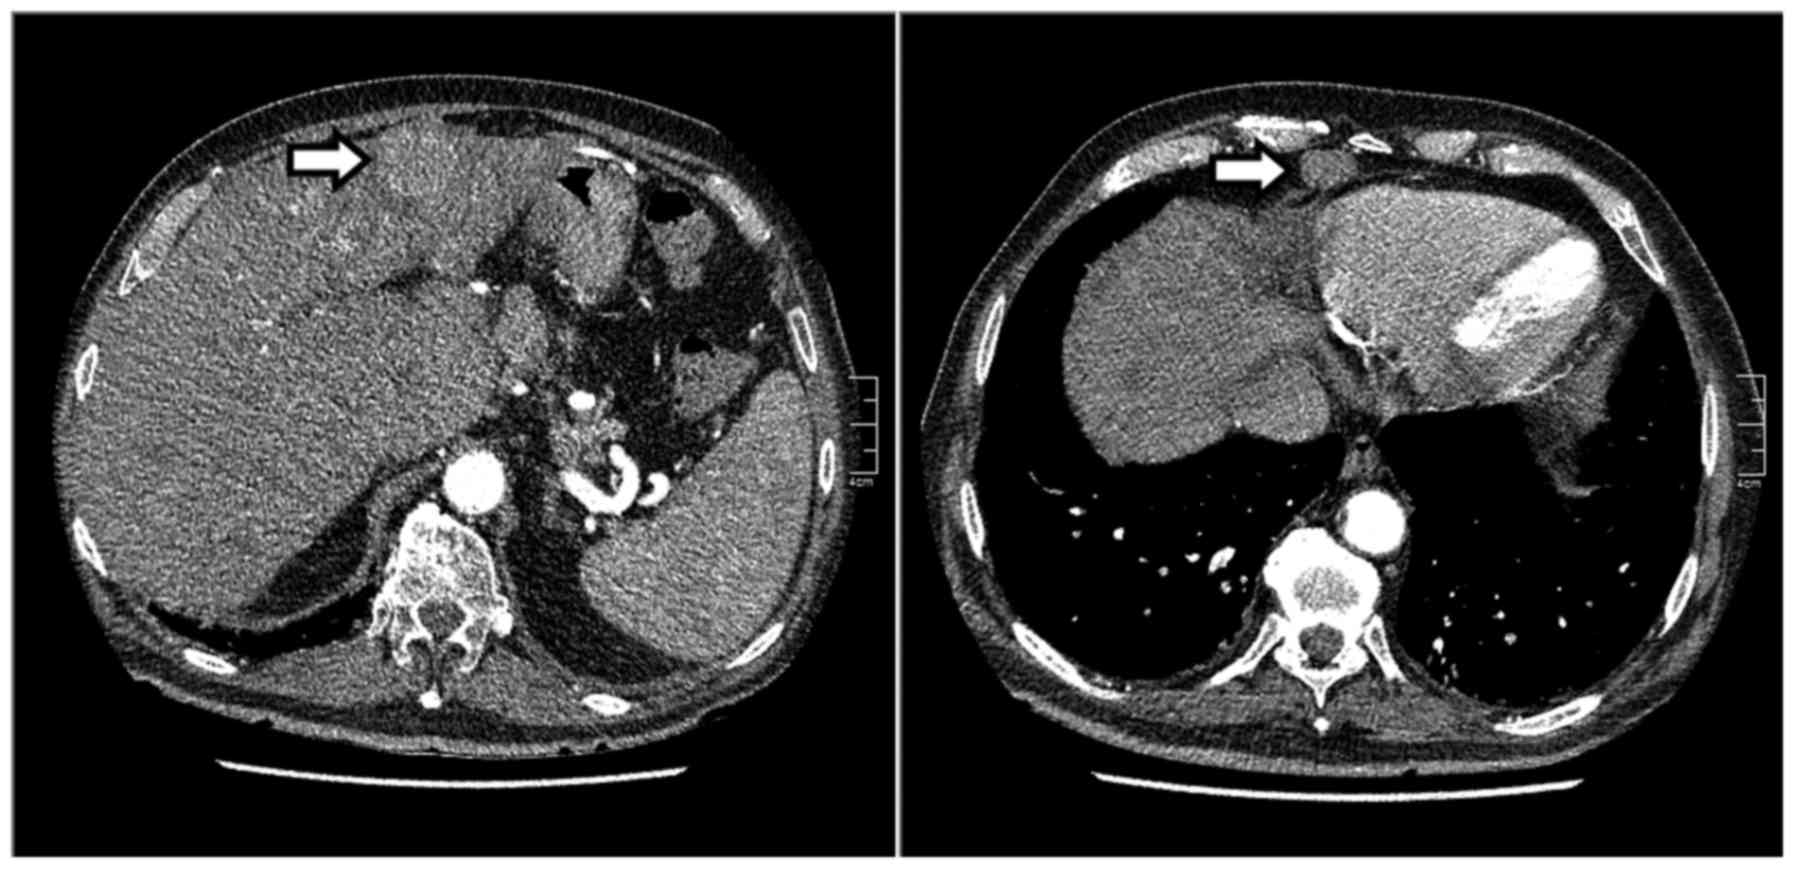

A computed tomography (CT) scan revealed multiple liver and lung lesions suspicious for metastases, peritoneal depositions, but no primary tumour (Fig. 1). An ultrasound-guided liver biopsy was performed. The biopsy revealed malignant cells positive for pancytokeratin, slightly positive for cytokeratin (CK) 7, α-fetoprotein (AFP), carbohydrate antigen-125 and CD-10, and negative for CK20, CDX-2, thyroid transcription factor-1, prostate-specific antigen, CK7 and monoclonal carcinoembryonic antigen (CEA), findings consistent with an undifferentiated carcinoma. Additional immunostaining was positive for hepatocyte paraffin 1 monoclonal antibody, and polyclonal CEA canalicular immunostaining was also present. Combined with a serum AFP level of >16,600 kU/l, the diagnosis of advanced HCC was established. Other laboratory tests are summarised in Table I. The patient had a poor performance status (WHO performance status 3) and declined any form of treatment. Therefore, he was referred to the general practitioner for supportive palliative care.

Figure 1.

Initial computed tomography images showing a suspicious hepatic lesion and a lesion appearing to be malignant anterior to the pericardium (arrows).